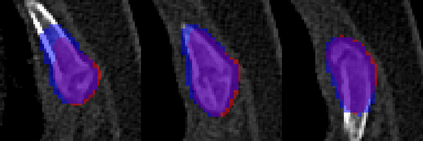

Rib fractures are a common and potentially severe injury that can be challenging and labor-intensive to detect in CT scans. While there have been efforts to address this field, the lack of large-scale annotated datasets and evaluation benchmarks has hindered the development and validation of deep learning algorithms. To address this issue, the RibFrac Challenge was introduced, providing a benchmark dataset of over 5,000 rib fractures from 660 CT scans, with voxel-level instance mask annotations and diagnosis labels for four clinical categories (buckle, nondisplaced, displaced, or segmental). The challenge includes two tracks: a detection (instance segmentation) track evaluated by an FROC-style metric and a classification track evaluated by an F1-style metric. During the MICCAI 2020 challenge period, 243 results were evaluated, and seven teams were invited to participate in the challenge summary. The analysis revealed that several top rib fracture detection solutions achieved performance comparable or even better than human experts. Nevertheless, the current rib fracture classification solutions are hardly clinically applicable, which can be an interesting area in the future. As an active benchmark and research resource, the data and online evaluation of the RibFrac Challenge are available at the challenge website. As an independent contribution, we have also extended our previous internal baseline by incorporating recent advancements in large-scale pretrained networks and point-based rib segmentation techniques. The resulting FracNet+ demonstrates competitive performance in rib fracture detection, which lays a foundation for further research and development in AI-assisted rib fracture detection and diagnosis.